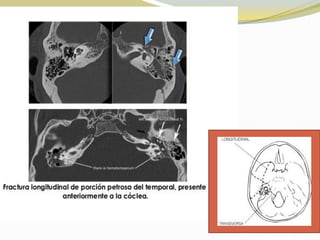

 Primera imagen muestra fractura no desplazada

 la segunda imagen muestra fractura desplazada

Longitudinal:

Estas fracturas cruzan sobre el techo del oído medio, entre

la cápsula laberíntica y el tejido óseo neumático

adyacente, se caracterizan por la presencia de otorragia.